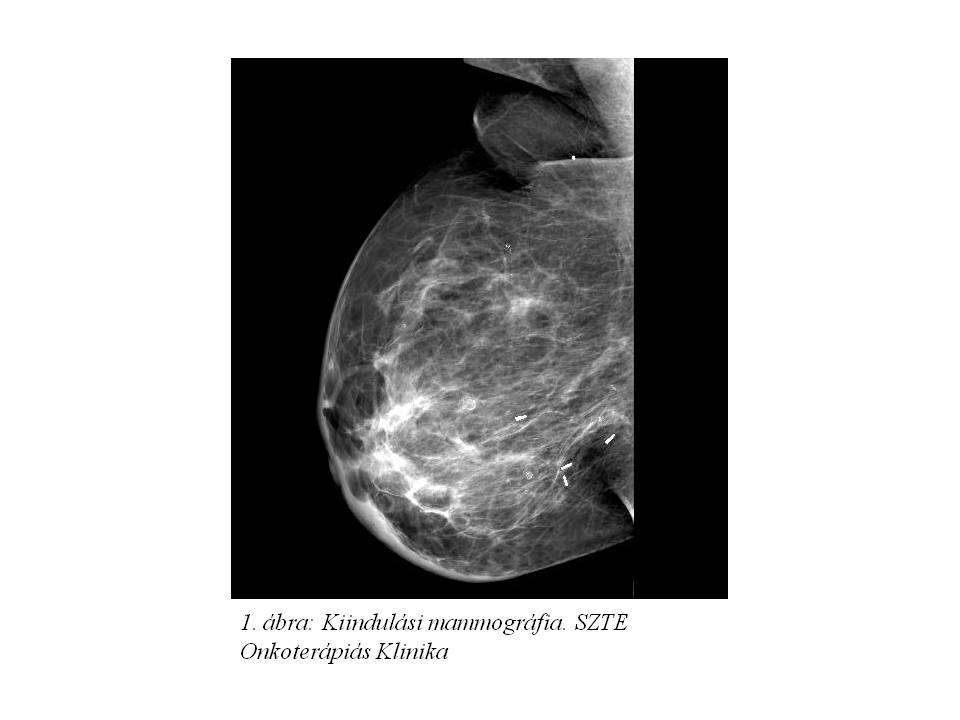

Postoperatív onkológiai kezelésként a jobb emlőállomány irradiatioját (25x2 Gy) végeztük 2010.07.15-től (2. ábra), melyet adjuváns szisztémás kezelésként tamoxifén terápia követett 2010.09.01-től.